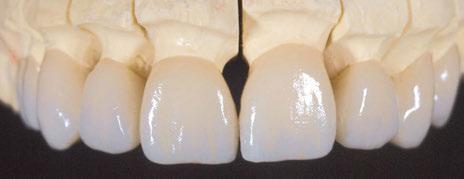

Protocolo Di2gitalArch® 2.0: Carga inmediata en el día en maxilar superior atrófico. Con Ziacom Galaxy, por el Dr. Luis Cuadrado Canals.